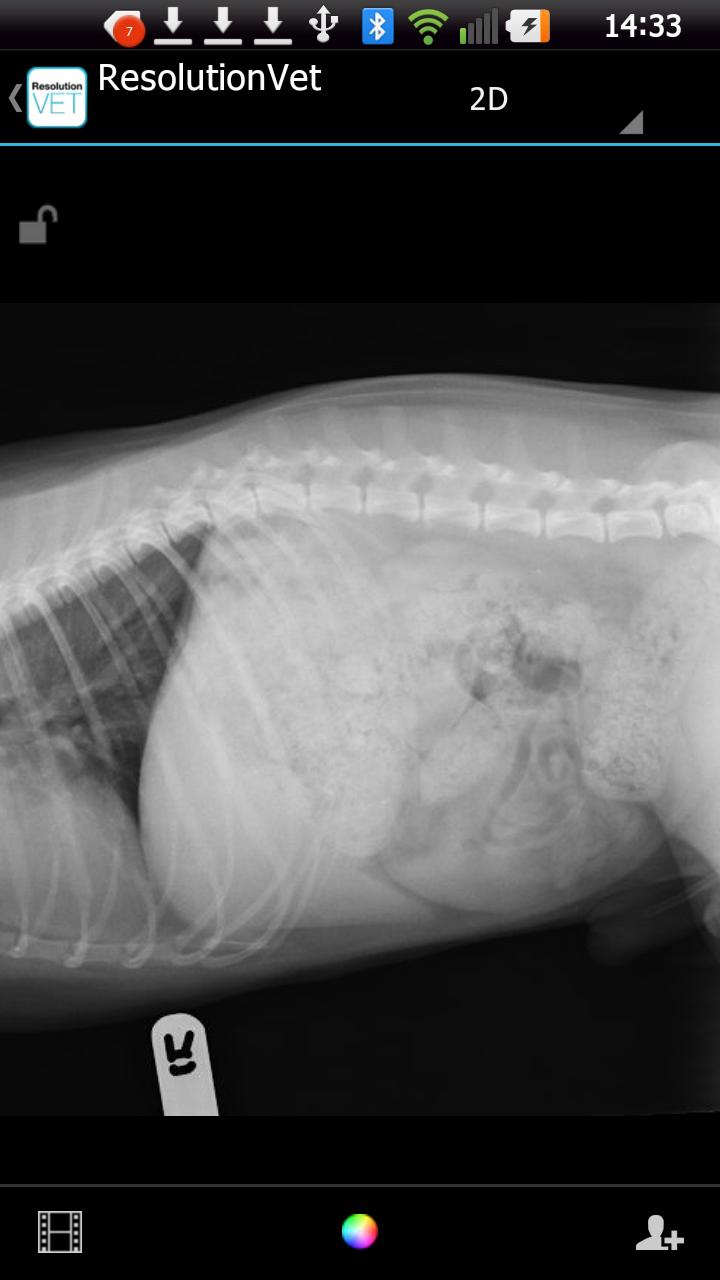

ResolutionVet permite a los médicos veterinarios ver de forma segura las imágenes de sus pacientes de una amplia gama de dispositivos móviles y colaborar con otros profesionales de cualquier lugar en tiempo real.

2d: ventana/nivel dinámico y presets de visualización

Este producto es solo para ver imágenes de radiología veterinaria.